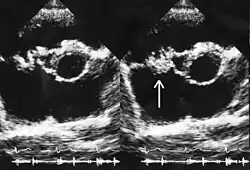

Infections of the central nervous system

In animal studies of meningitis caused by Streptococcus pneumoniae, linezolid was found to penetrate well into cerebrospinal fluid, but its effectiveness was inferior to that of other antibiotics.[54][55] There does not appear to be enough high-quality evidence to support the routine use of linezolid to treat bacterial meningitis. Nonetheless, it has been used successfully in many cases of central nervous system infection—including meningitis—caused by susceptible bacteria, and has also been suggested as a reasonable choice for this indication when treatment options are limited or when other antibiotics have failed.[56][57] The guidelines of the Infectious Diseases Society of America recommend linezolid as the first-line drug of choice for VRE meningitis, and as an alternative to vancomycin for MRSA meningitis.[58] Linezolid appears superior to vancomycin in treating community-acquired MRSA infections of the central nervous system, although very few cases of such infections have been published (as of 2009).[59]